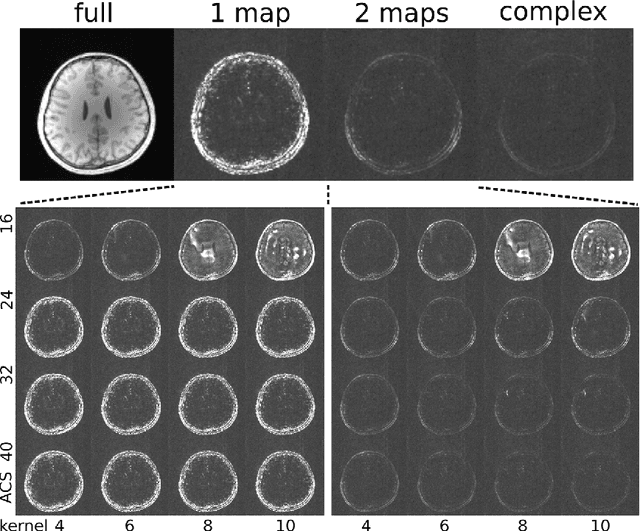

Purpose: To develop an ESPIRiT-based method to estimate coil sensitivities with image phase as a building block for efficient and robust image reconstruction with phase constraints. Theory and Methods: ESPIRiT is a new framework for calibration of the coil sensitivities and reconstruction in parallel Magnetic Resonance Imaging (MRI). Applying ESPIRiT to a combined set of physical and virtual conjugate coils (VCC-ESPIRiT) implicitly exploits conjugate symmetry in k-space similar to VCC-GRAPPA. Based on this method, a new post-processing step is proposed for the explicit computation of coil sensitivities that include the absolute phase of the image. The accuracy of the computed maps is directly validated using a test based on projection onto fully sampled coil images and also indirectly in phase-constrained parallel-imaging reconstructions. Results: The proposed method can estimate accurate sensitivities which include low-resolution image phase. In case of high-frequency phase variations VCC-ESPIRiT yields an additional set of maps that indicates the existence of a high-frequency phase component. Taking this additional set of maps into account can improve the robustness of phase-constrained parallel imaging. Conclusion: The extended VCC-ESPIRiT is a useful tool for phase-constrained imaging.